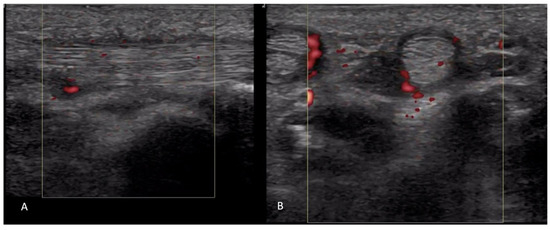

2.1.2. Inflammatory Arthritis

2.4. Vascular Pathology

2.5. Skin Thickening